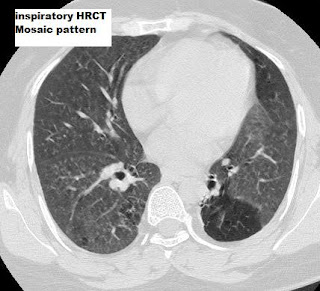

The ATLANTIS study was designed to identify the combination of physiological and imaging variables that best measure the presence and extent of small airway disease in asthma, both cross-sectionally and longitudinally.Causes of airway obstruction.Sie hatte mit verschiedenen Methoden das Ausmaß der small airway disease (SAD) sowie den Zusammenhang zwischen SAD und Asthma-Schweregrad bei 800 Asthmatikern untersucht.Pathogenetisch spielt beim zentrilobulären Lungenemphysem eine chronisch destruktive Bronchiolitis (small airway disease) die entscheidende Rolle.Small airways disease (SAD) is being increasingly recognized as a key pathological feature of COPD.Learn about the definition, pathology and radiographic features of small airways disease, a group of conditions that affect the peripheral airways.

Disease Medicine and Dentistry 100%.Imaging of small airways disease and chronic obstructive pulmonary disease. Inflammatory small airways disease may exacerbate small airways injury and dysfunction through mechanical stresses of cyclic opening and closing of airways during tidal breathing.Schlagwörter:Small Airways DiseaseSmall Airway Disease and Copd While some authors .Dieser Artikel beschreibt die Möglichkeiten, die kleinen Atemwege gezielt zu erreichen, um verschiedene Lungenerkrankungen zu behandeln. 2009; Berniker AV, Henry TS.Small airway disease syndrome is described in numerous disease states using a multidisciplinary approach. Constrictive Bronchiolitis Keyphrases 100%. Häufig stehen chronisch entzündliche Veränderungen am .Bei schwer kontrollierbarem Asthma sind oft die kleinen Atemwege betroffen.

Studies have brought forward pathological evidence of . Find chapters and articles on respiratory . How mucus protects your body.Is asthma predominately a disease of the large or small airways? The question has vexed these pages for at least 50 years (1–4) and although a consensus appears to be emerging in favor of a substantial role for the small airways, the recent evidence is scarcely more conclusive. Das e-Journal Journal für Pneumologie steht als PDF-Datei (ca. Imaging of Small Airways . Bronchiolitis Obliterans Medicine and Dentistry 100%. Small airways disease . airways that are more peripheral to the main bronchi and proximal bronchioles (4 th the 14 th generation) – arbitrarily considered to be those with an internal diameter of ≤2 mm 3). The increased understanding of the processes underlying the development of small airways disease should facilitate pharmacological intervention targeted at this hitherto neglected . Federico Lavorini PhD; 3. But then it gets .Small airways disease has been related to asthma control, severity, and risk of exacerbation.Small airway dysfunction in obstructive lung disease was hallmarked in the 1960–1970s [21, 22], but details were limited to existing invasive studies [19, 20], and documentation of resistance changes after early childhood [] with statements of the “lungs quiet zone” in the mid-last century [13,14,15,16, 20,21,22]. Bronchiolitis starts out with symptoms much like a common cold. Noninvasive techniques including spirometry, plethysmography, nitrogen washout, impulse oscillometry, and cross-sectional imaging .Aspekte der „Small Airway Disease“ in Asthma und COPD Lambers C Journal für Pneumologie 2013; 1 (1), 9-10.2 Small airways, i. In recent years, there has been a renewed interest in the early .This study highlights the small airways disease that occurs in patients with mild and moderate COPD, which could not be measured previously, and highlights the . • Patients with COPD and small airways disease have worse spirometry results, more severe lung hyperinflation, and poorer health status compared with those without small airways disease, making the . Histologische Untersuchungen haben dies eindrucksvoll schon in den 1960er Jahren gezeigt.The peripheral airways are the respiratory tract regions that are most exposed to pollutants, cigarette smoke, and noxious agents.Why We Should Target Small Airways Disease in our Management of COPD: A Review .Schlagwörter:Small Airway Disease in LungsEarly Small Airway Obstruction, the peripheral airways with diameter less than 2 mm (), are the main site of increased airway resistance in asthma3 and numerous studies have correlated small .ein „air trapping“ im Rahmen einer „small airway disease“ geben. Data demonstrated a relationship between small airway disease to development of symptoms, inhaled toxin exposure, presence of local and systemic inflammation, histologic abnormalities, and response to therapy.Schlagwörter:Small Airway DiseasePublish Year:2019